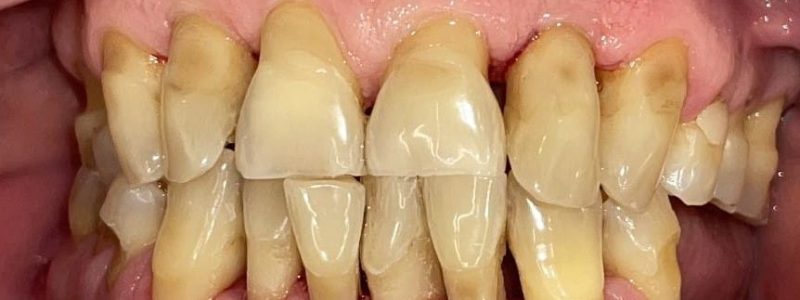

Redarea funcției masticatorii și estetice prin restaurări complexe cu ajutorul coroanelor pe implanturi tip FP1, cu aspect natural si sănătos al gingiei.

Boală parodontală tratată cu menținerea unor dinți și înlocuirea celor irecuperabili cu implanturi.